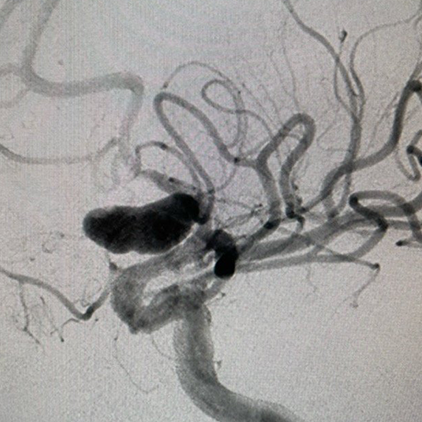

We provide devices and treatment of complex brain aneurysms and vascular malformations free of cost. These are some of the complex brain aneurysm we have recently treated in Pakistan. Devices and catheters used for all procedures were provided by Pakistan Stroke Initiative, and in some cases charges for hospitalization as well.

Although we typically don’t take photos of our patients and their families, many of those we have treated have made special requests for it. Visiting physicians from abroad have consistently been impressed by the gratitude and appreciation shown by our patients and their families for the care they receive.

All of these photos have been shared with the permission of the patients and their families.